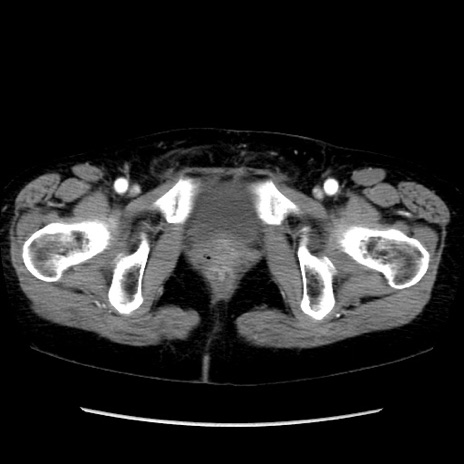

症例32(横断像)

【症例】40歳代 女性

【主訴】上腹部痛、嘔気・嘔吐

【現病歴】約9時間前頃から急に上腹部痛、嘔気、嘔吐が出現。改善しないため救急要請。

【既往歴】子宮頚癌(広汎子宮全摘術、放射線療法)、腸閉塞